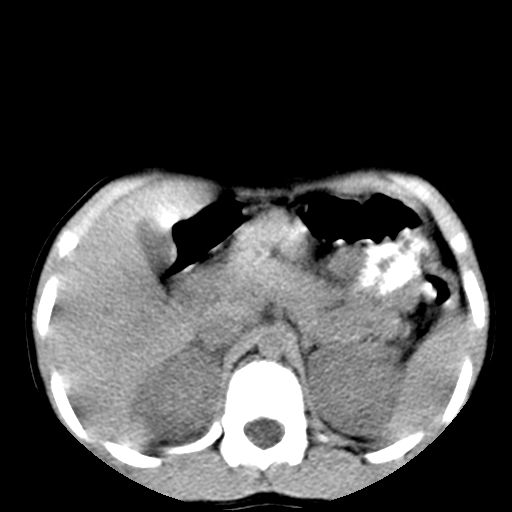

腹部好象未见异常。

腹部ct平扫未见明确异常

腹部ct平扫不能提示哪里有病变。